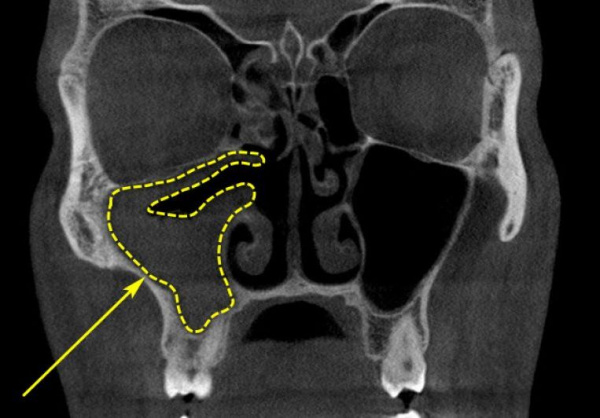

Одонтогенный синусит

На долю одонтогенного гайморита приходится от 10 до 30% случаев всех инфекций верхнечелюстных пазух. Острый синусит манифестирует с головной боли, температурной реакции, ощущения давления в проекции соответствующей пазухи. Нарастает отечность полости носа, затрудняется дыхание, снижается обоняние. Через некоторое время из пазухи начинает отделяться слизисто-гнойный или гнойный секрет. Мягкие ткани подглазничной области и щеки выглядят припухшими.

- Рентген. Для оценки местных изменений зубных и костных тканей выполняется ОПТГ, рентгенография челюсти, придаточных синусов, мягких тканей шейной области. При планировании оперативного вмешательства рентгеновская диагностика дополняется КТ и МРТ соответствующих областей.

- ЛОР-осмотр. Наряду с рентгеновской визуализацией выполняется эндоскопическое обследование: риноскопия, эндоскопия носа, синусоскопия. При необходимости прибегают к диагностической пункции верхнечелюстной пазухи.